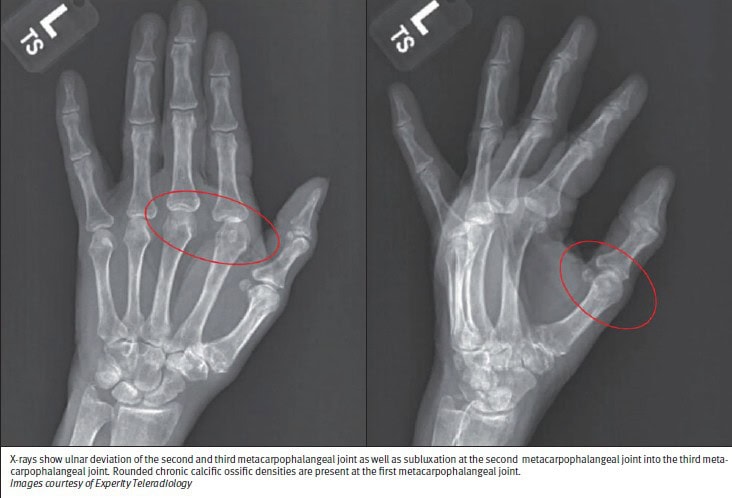

Radiographic imaging of the hands, wrists, feet, or knees will demonstrate the presence and extent of joint space narrowing, bony erosion, ankyloses (fusion), subluxation, and joint mutilation, all of which are characteristics of RA (Images 1-2).1 These images may include posteroanterior or anteroposterior, lateral, and oblique, however, a scaphoid view of the wrist may be ordered. Radiologically, RA often exhibits lateral erosion, distinguishing it from OA, which typically demonstrates central erosions. Bony erosion in early RA is not usually detectable on plain radiographs, therefore utilizing ultrasound or magnetic resonance imaging with contrast would be of better utility.1, 12

An x-ray of the hands and wrists was performed, which showed joint space narrowing within MCPJs, bony erosions in the carpal bones, and periarticular osteopenia in the interphalangeal joints. When calculating a rheumatoid arthritis classification criteria score, it was positive for indication of rheumatoid arthritis.

In the urgent care, radiographs demonstrated joint space narrowing within MCPJs, bony erosions in the carpal bones, and periarticular osteopenia in the interphalangeal joints. The 2010 ACR-EULAR score of 6 for this patient assisted with RA diagnosis. The patient was given ibuprofen and acetaminophen to decrease the inflammation in the joints and manage pain. She was given a referral to a rheumatologist and physical therapy to help with decreased range of motion. The rheumatologist ordered antinuclear antibodies, C-reactive protein, erythrocyte sediment rate, RF, and ACPA to set a baseline for disease and develop a treatment plan. The rheumatologist prescribed methotrexate monotherapy for the patient.